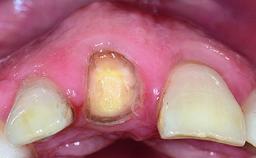

Replacement of an Ankylosed Upper Left Central Incisor: Bone Augmentation and Socket Grafting, Late Placement of an RC Bone Level Implant

A 15-year-old male patient was referred to us by his pediatric dentist in June 2004 for evaluation of treatment options for his failing tooth 21. The patient had recently seen an endodontist for internal bleaching and been advised that there had been significant resorption and ankylosis. The patient’s mother was concerned because the tooth appeared shorter than the adjacent one. His past dental history was significant for trauma (September 2001), where the tooth had been avulsed and reimplanted. Teeth 11 and 21 had been endodontically treated.

Bone Volume Deficient horizontally, requiring prior grafting